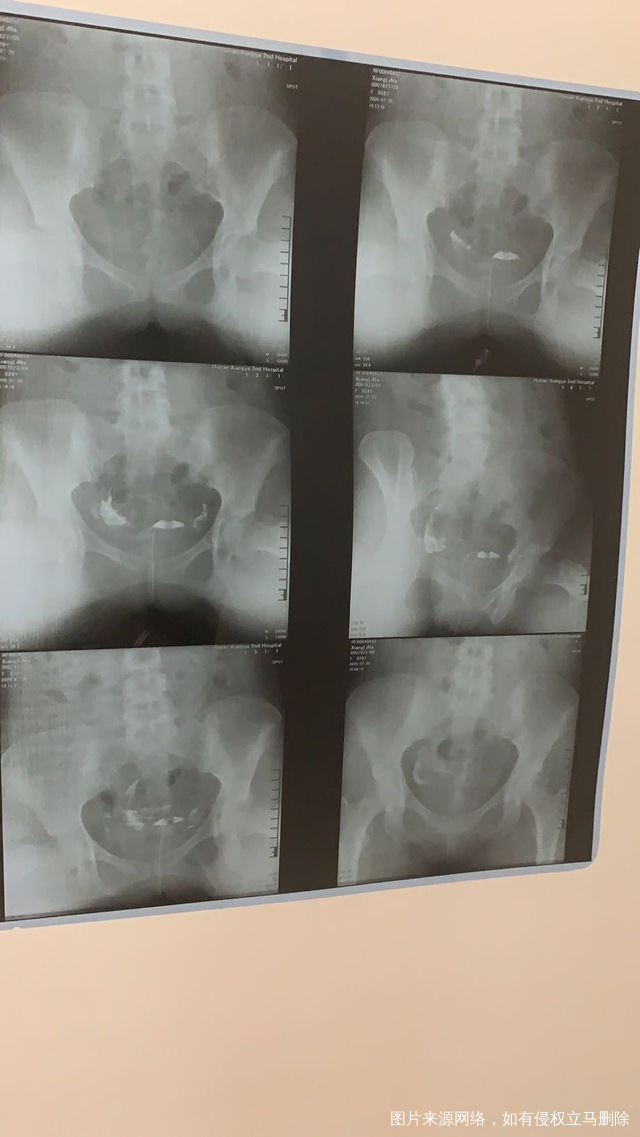

做完输卵管造影第六天了小腹还是感觉沉甸甸的如